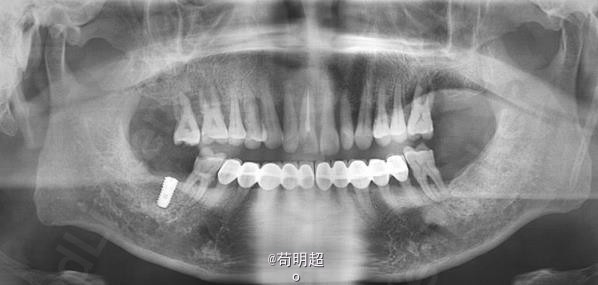

47牙齿种植修复

患者满意,效果很好。